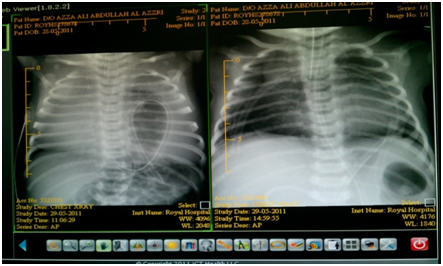

A female baby of 39 weeks’ gestation, was born on 28.5.2011 with birth weight 2.72 Kg and good APGAR scores. She was admitted to the neonatal nursery as the antenatal ultra sound scan had shown diaphragmatic hernia. Post- natal chest X ray was reported as left diaphragmatic hernia (Figure 2). Echocardiography showed a VSD.A single large vessel was seen to divide into abnormal aorta and narrow pulmonary vessels with the impression of corono-truncal anomalies of the heart. The impression on echocardiography was that the baby had a complex heart disease with pleural effusion. After preoperative stabilization, the bay was operated. Operative findings were a large anterior diaphragmatic hernia without a sac; within the pericardium, pushing the heart posterior and superiorly. The contents of the hernia were stomach, transverse colon and the left lobe of the liver. This was closely adherent to the edge of the defect and could be separated. Posterior rim of the defect was just less than one cm from the IVC. There was no pericardial effusion. The contents were reduced. A silicon tube was inserted into the pericardial cavity as a pericardial drain and connected to under water seal set. The anterior rim of the defect was sutured with the posterior rim with 3/0 silk interrupted sutures. The baby was shifted to neonatal nursery after extubation in operating theater itself. She was discharged on the 12th day post- operative in good condition.

Figure 2  Shows left sided congenital diaphragmatic hernia without pericardial effusion (left side film) and the large size of the remnant of the pericardial sac after surgery which is delineated by the tube drain (right side film).

Anterior retro-sternal (Morgagni) congenital diaphragmatic hernia is rare in regard to all types of congenital diaphragmatic hernias. Inter-pericardial congenital diaphragmatic hernia as a variant of Morgagni hernias are very rare. The counted cases published until now are 19 cases in addition to our two cases makes them total of 21 cases. It can be misdiagnosed pre-operatively as left congenital diaphragmatic hernia like our second case if we depend only on the AP view of the x-ray. Apart from requiring nasal oxygen for tachypnea, the cases were born stable.